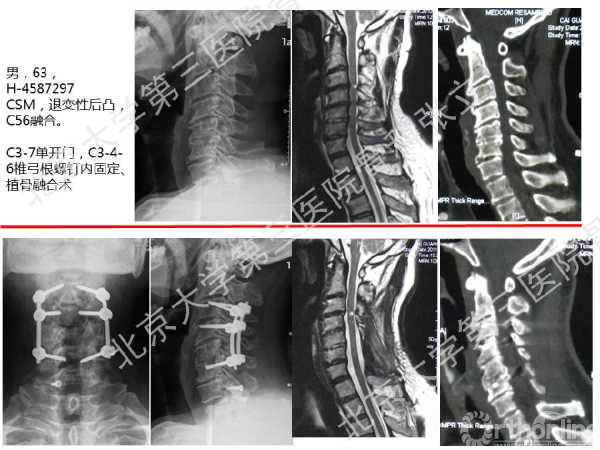

徒手置钉的下颈椎椎弓根钉技术对于很多骨科同道来说,无疑是难度超高、不敢触及的一项技术。已熟练掌握这一技术的北京大学第三医院骨科张立主任医师认为,下颈椎椎弓根钉徒手置钉技术固定可靠,能满足绝大多数后路固定所需,可应用于脊柱外伤、脊柱畸形、脊柱肿瘤,以及CSM伴退变性颈椎后凸畸形。它的优势是:螺钉尾部靠外,不影响椎板成形术;先置钉固定,后开门,更安全;和椎板成形术完美结合,减压、复位、固定一次完成;极少出现脊髓、神经根及椎动脉损伤。